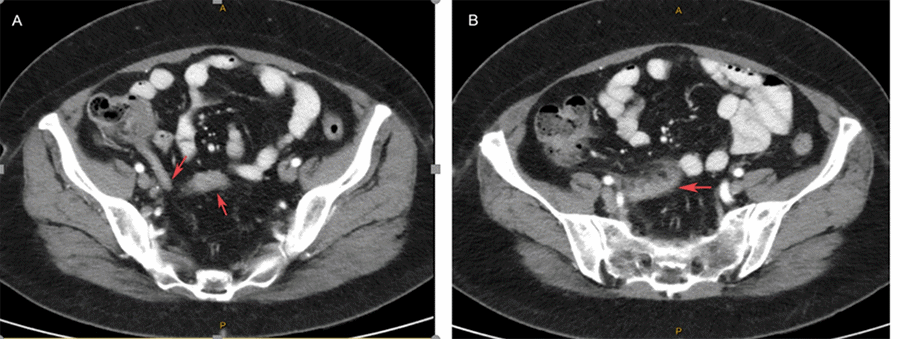

Figure 5. Histology Showing Ruptured Appendiceal Diverticulum with Extravasated Mucus in Cavity Surrounded by Inflamed Fibrogranulation Tissue Devoid of Lining Mucosa. Published with Permission

Not uncommonly, patients with appendiceal diverticulitis present with more complicated disease such as perforation. This event occurs in up to 66% of cases at a rate four times greater than the incidence seen in acute appendicitis.3,7 Typically, the perforation occurs into the mesoappendix and is retroperitoneal as the acquired diverticulum is mostly mesenteric in location.7,9 Critically, a mass resulting from perforation into the mesoappendix may be mistaken for carcinoma, a finding which was mirrored in our patient. Of greatest concern are the reports from some series about a possible link between appendiceal diverticulosis and appendiceal neoplasms,4,7,8,11 although the explanation for this link remains unclear.